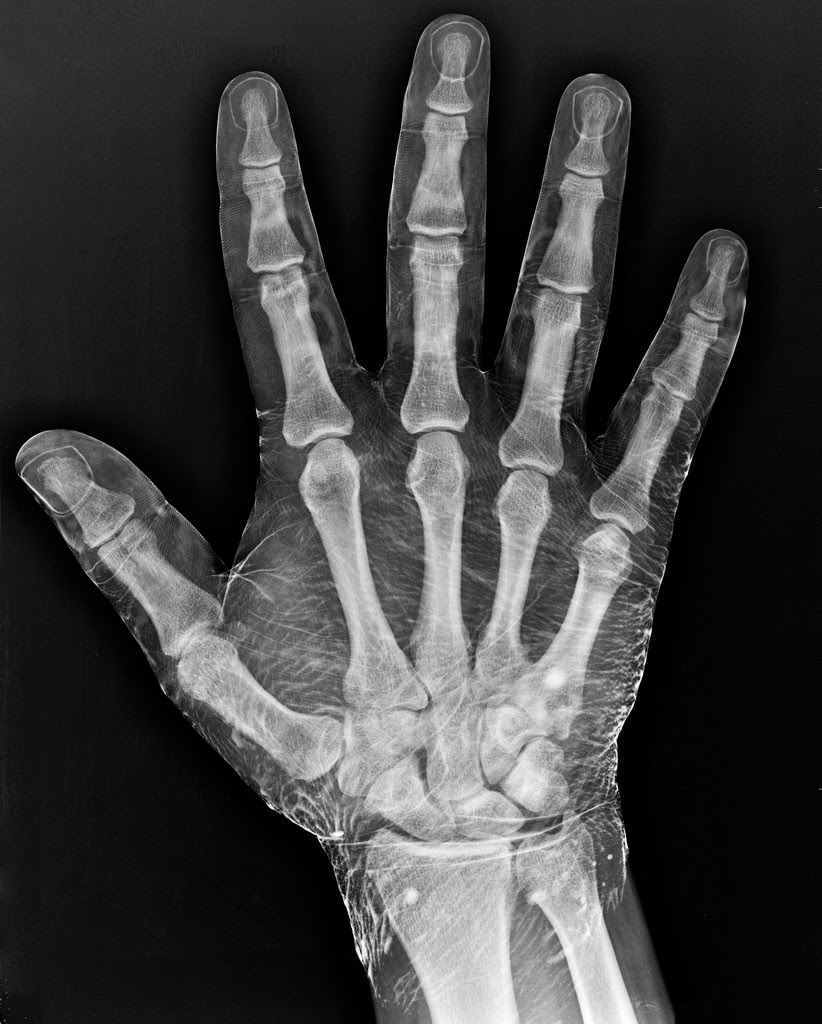

Radiograph of a hand dipped in iodine.